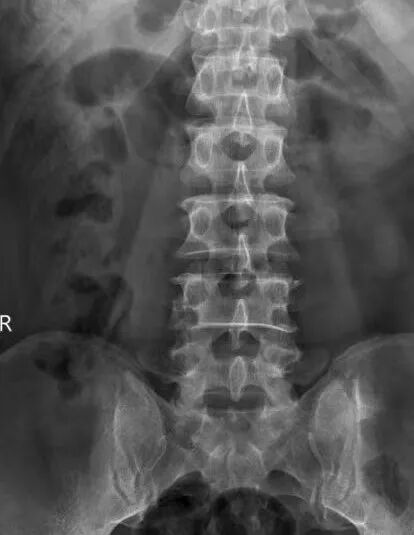

患者江先生,56岁,因外伤4椎体压缩性骨折。为了最大限度减少对患者的创伤,加快其康复,术前科室进行认真讨论,查阅资料,观看手术视频,制订详细的手术计划,于929日在全麻下行微创小切口脊柱后路钉棒系统内固定术治疗腰4椎体压缩性骨折,术后复查X线提示腰椎高度恢复,内固定位置正常。